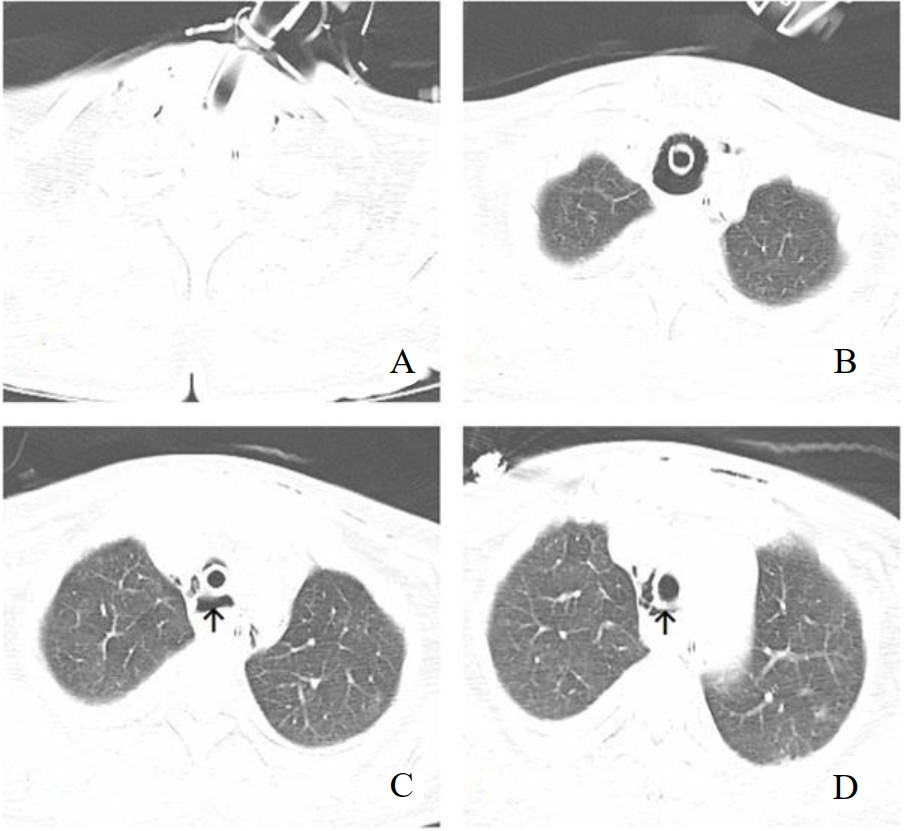

采用Griggs[1]操作技术,器械(型号PW16-S-80-C)由上海全安医疗器械有限公司提供。Seldinger穿刺成功后放入导丝,专用扩张钳扩张皮下组织和气管前壁,置入气管切开套管。放置套管后拔除导丝,导丝出现弯曲,气管切开套管未见气体溢出,考虑气管切开套管异位,再次尝试2次,未能成功置入气管切开套管。后经纤维支气管镜通过气管插管口入镜实时观察,先经切口处放入导丝,在导丝引导下置入气管切开套管,纤维支气管镜证实气管切开套管在位并吸除气道内痰液和血液。术后第2天复查胸部CT提示:纵隔和颈部少许积气,气管切开套管开口层面正后方可见气腔(图 1)。第3天患者出现肺顺应性下降,潮气量降低,吸痰管难以进入,气道内吸出少量血性痰。考虑出现紧急气道情况,立即行床边纤维支气管镜检查,经气管切开套管入镜,见软骨环,膜部有血凝块,经过气管切开套管下约1~2 cm后纤维支气管无法伸入远端,考虑血凝块伴多发纤维素样组织形成,血凝块无法吸出,试用活检钳捣碎血凝块亦未能吸出。患者肺顺应性差,高参数机械通气[压力控制通气(PCV)模式,吸入氧体积分数100%,PEEP 12 cmH2O(1 cmH2O=0.098 kPa),高于PEEP压力控制20 cmH2O,吸呼比1∶2,呼吸频率14次/min] 经皮氧饱和度约94%。当时因为极度担心血块完全阻塞气道,所以在负压状态拔除气管切开套管重新置入后通气明显改善,纤维支气管镜证实气管切开套管在位,未见血凝块。为明确原因,笔者予可视喉镜联合纤维支气管镜引导下经鼻气管插管成功,同时拔除气管切开套管,在纤维支气管镜(经鼻气管插管入镜)监视下逐渐地外拔气管插管,可见气道约6点钟方向气管膜部假腔形成,撕裂起始部位约在气管切开套管管口附近。后再次经鼻入镜,经过声门后气管插管气囊放气,经气管插管旁路入镜观察膜部假腔情况。笔者推测患者气管切开套管角度改变(往正后方方向),此时大部分气管切开管口对准假腔,护士吸痰管进入假腔,反复多次吸痰导致组织损伤伴出血,血凝块形成,负压状态下拔出气管切开套管时把血凝块带出,再次置入时幸运地置入气管真腔。为建立确切有效的人工气道,考虑重新留置气管切开套管有再次置入假腔可能,且常规气管切开套管难以通过真假腔分隔处,予逐渐外拔气管插管尖端水平位至气切口上方,在纤维支气管镜引导下经皮肤切口置入加长型气管切开套管,经纤维支气管镜证实气管切开套管尖端通过假腔分隔处,患者肺顺应性明显改善,吸痰管吸痰通畅。纤维支气管镜检查见图 2。

| A:颈部少许皮下气肿;B:气管切开套管气囊部位未见明显异常;C:气管切开套管开口层面可见少许纵隔气肿,正后方可见气腔;D:气切套管下约1 cm层面,见气腔缩小;箭头示气腔 图 1 患者经皮扩张气管切开术后胸部CT |